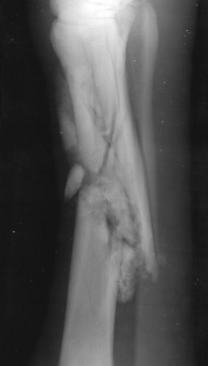

New cards

Common location for a spiral fracture

Tibia